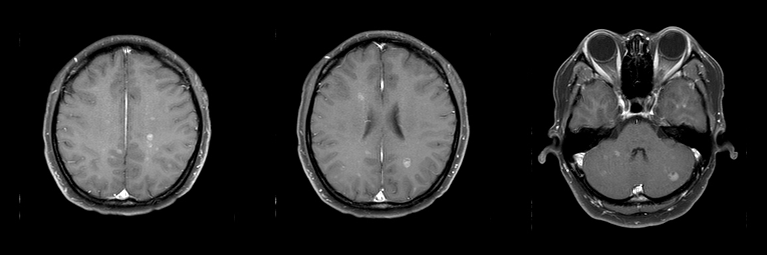

• 头颅MR(2024年4月14日):颅内多发结节状异常信号,大者位于左侧小脑板球,大小约1.1cm×1.0cm,M灶可能,请结合临床。

图 2024年4月14日头颅MR

• 头颅MR(2025年3月27日):颅内病灶较前明显减少,余左侧小脑半球结节状异常信号,余显示不清,请结合临床。

图 2025年3月27日头颅MR

• 头颅MR(2025年10月18日):脑实质平扫增强未见明显异常。

图 2025年10月18日 头颅MR

①治疗11个月后,2025年3月27日颅脑MR对比2024年4月14日颅脑MR,患者脑部转移灶减少,左侧小脑半球处病灶明显减小,达到部分缓解(PR),患者眩晕症状消失。

②治疗18个月后,2025年10月18日颅脑MR对比2025年3月27日颅脑MR,患者脑转移灶消失,未见明显异常信号,达到CR,患者生活质量良好,药物耐受性好。